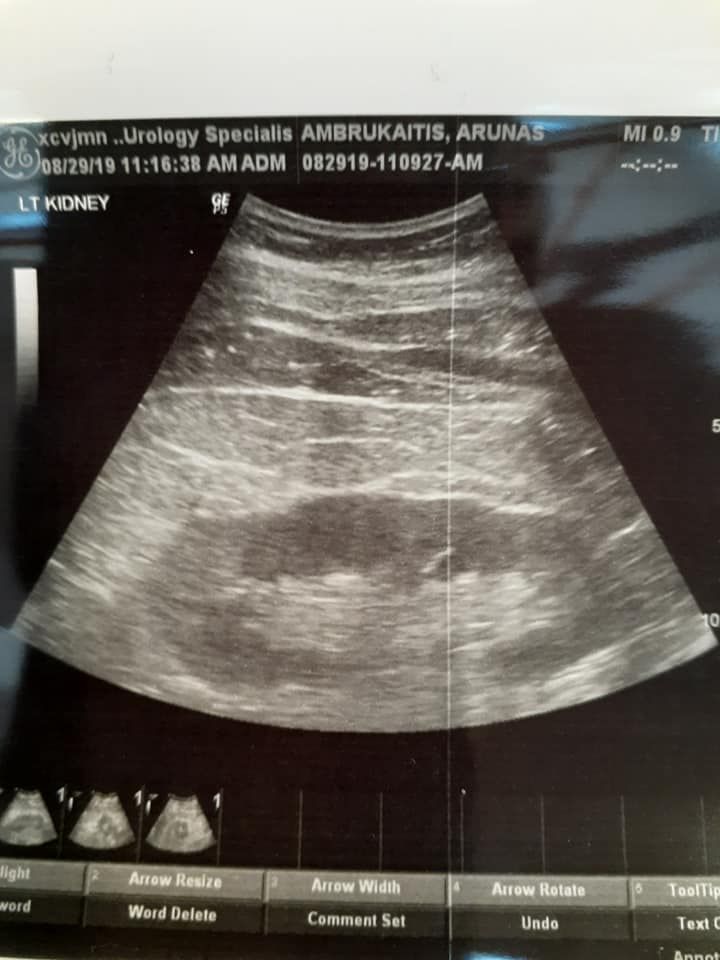

08/15 I was diagnosed with 3 mm stone in the L.kidney. 2 weeks latter ultrasound proved effect of healing with codes method.